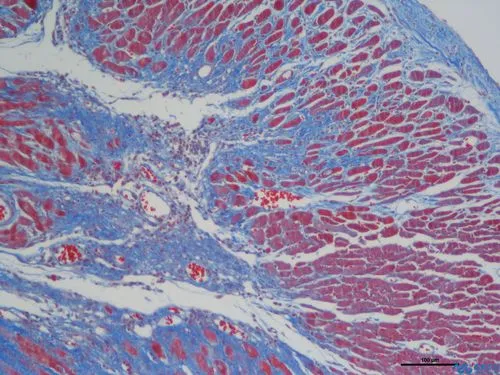

完成以上步驟后,切片中的膠原纖維、黏液和軟骨將呈現(xiàn)藍(lán)色(如果使用淺綠色液體,則呈現(xiàn)綠色),細(xì)胞質(zhì)、肌肉、纖維素和神經(jīng)膠質(zhì)將呈現(xiàn)紅色,而細(xì)胞核將呈現(xiàn)黑色和藍(lán)色。